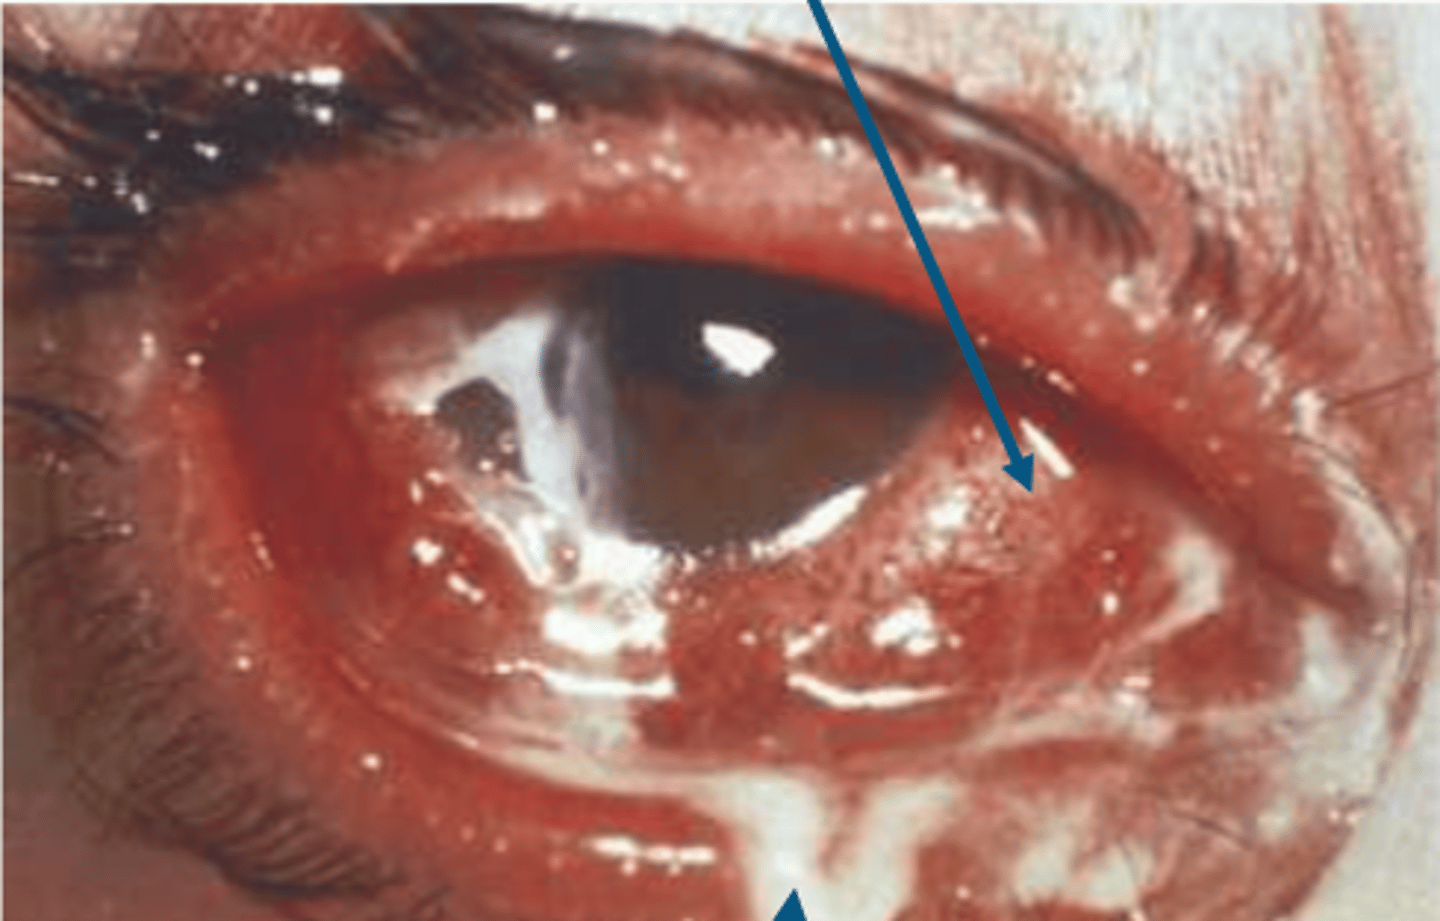

_____ is rapidly progressive severe conjunctivitis characterized by copious purulent discharge and lid edema accompanied by (+) ___ node

in hyperacute conjunctivitis, the presentation is

1. diffuse conjunctival hyperemia & chemosis

2.purulent discharge which is made of pathogen, wbc, dead cells

in hyperacute conjunctivitis, there is a risk of ___ and ____ which is the severe inflammation of the eye affecting all layers including retina, cornea, and sclera

perforation, panophthalmitis

clinical signs for hyperacute conjunctivitis includes (7)

1. severe purulent discharge

2. + PA node

3. papillae

4. severe lid edema

5. SPK/erosions

6. infiltrates

7. risk for rapid corneal ulceration which lead to perforation